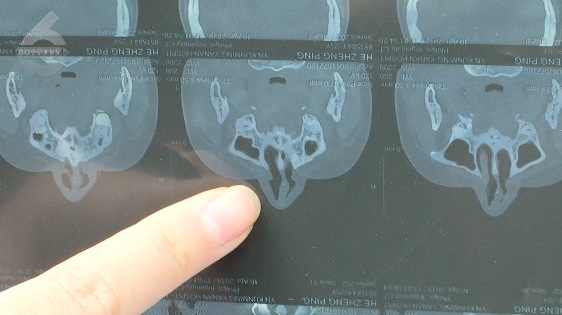

何女士说:“从2015年开始,艺星整形拖了我5年3个月,我在延安医院做了检查,医生说可能是鼻小柱导致的呼吸不畅,要解决根本问题,才能解决我呼吸的问题。”